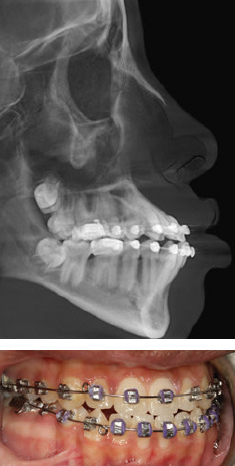

CHAPTER Orthognathic surgery involves the surgical manipulation of the elements of the facial skeleton to restore the normal anatomic and functional relationship in patients with anomalies of the dentofacial skeleton. Since its evolution from the mid-20th century with its classic procedures to the incorporation of distraction, osteogenesis has become a powerful tool in the surgeon’s armamentarium that can create dramatic changes in facial form and function that few other procedures can achieve. Achieving this desired goal involves a detailed architectural blueprint and construction details. Furthermore, it requires a close working relationship between the orthodontist and the surgeon, each manipulating their own component of the dentofacial unit in a complementary, time-specified, integrated approach. Speech and language pathologists and psychologists play an important role in guiding the treatment planning. As an elective procedure, orthognathic surgery places significant demands on patients and their families—with an overall length of treatment that spans years—in the form of financial resources and a multitude of appointments that require time off from employment and educational activities beyond the brief period of surgery and its immediate recovery. It is a significant commitment from the patient, caregivers, and professionals. Thus, practitioners must clearly define the surgical and dental goals and then concisely translate those goals to the patient and the family, including a discussion regarding why those goals may not be reached. The probable is what usually happens, but at this point the focus should be on the improbable, the unintended, and the unexpected. Thus understanding the unfavorable outcomes and surgical and orthodontic complications that can and do occur with maxillofacial skeletal procedures is the subject of this chapter. There is a relevant distinction between the “unfavorable” and the “complication.” An unfavorable outcome can occur without a specific complication, and not all complications lead to an unfavorable outcome. A perfectly well-executed orthognathic procedure from blueprint to construction without any complications can still lead to an unfavorable or unsatisfactory outcome. A face with a perfect occlusal and functional result may not be pleasing to either its owner or to the architects who designed it. Moreover, unlike many surgical procedures, the outcome depends not only on the surgical procedure itself, but also on a multitude of factors that exist long before the actual surgery, as well as on the ability to control variables long after the surgical procedure has taken place. Whether the desired long-term outcome is achieved in terms of occlusal function and aesthetics of the dental and facial form depends on whether the goals of each of the phases of treatment were achieved. Moreover, the success of each phase depends on the preceding phase of treatment. For example, inadequate incisor decompensation limits the amount of sagittal repositioning possible and compromises the final facial aesthetics. If mobilization of the maxilla at the time of surgery is inadequate and a less-than-ideal occlusal relation obtained, the postsurgical orthodontic phase is prolonged, and relapse toward the initial condition is likely to occur. Even when facial skeletal and dental goals are achieved, the functional goals may not be. Moreover, unintended consequences may occur in terms of velopharyngeal insufficiency, airway compromise, or oromotor function while optimizing facial appearance. Each orthognathic case has a stepwise sequence of diagnosis, dentosurgical treatment planning, presurgical orthodontic preparation, surgery, postsurgical orthodontic detailing, and retention. Thus, unlike many of the surgical procedures, the scale of time is not measured in weeks to months; rather, it is measured in years. The surgical component must be taken within the context of the overall treatment from diagnosis to retention. Within this lengthy time frame of a complex choreography between orthodontist and surgeon, errors occur and accumulate. The list of errors that can lead to unfavorable outcomes and complications is extensive and is well reviewed in the existing literature.1–5 A meaningful way to discuss these is to consider what can go wrong with each phase of treatment (see the Summary Box). Unfavorable outcomes occur primarily because of poor communication between the surgeon and the orthodontist and the patient6,7 (Fig. 43.1). For the vast majority, patients are referred to the surgeon by the orthodontist, whose goal is primarily to achieve occlusion that cannot be achieved without the aid of the surgeon. The surgeon assesses the patient from the perspective of optimizing the aesthetic goals of the soft tissue draping the skeletal framework within the context of achieving the orthodontist’s expected occlusion (Fig. 43.2). Each must understand the other’s objective and abilities to achieve those goals within any limitations or compromises that may occur when reaching common surgical and occlusal goals. Moreover, anatomic dentosurgical goals may negatively affect functional goals. An example is a patient with a severe class III cleft in whom a maxillary advancement procedure may put the patient at risk for velopharyngeal incompetence (VPI) while improving the anterior dental relationship, the aesthetic appearance, and speech articulation. A mandibular setback procedure used to minimize VPI may put the patient at risk for obstructive sleep apnea and a less-than-ideal facial appearance. Thus the goals of the speech and language pathologist and sleep medicine specialist may come into play. In many cleft patients, the lateral incisor is not present, and incorporating the need for either prosthodontic consideration or segmental closure with a canine-to-lateral substitution needs to be addressed from the beginning. It is more than simply filling a dental gap, because each approach will have a different outcome in perioral aesthetics of the arch form and smile. In a patient with a class II cleft in whom significant mandibular advancement would improve both aesthetic appearance and airway, the surgeon’s goal may be limited by insufficient dental decompensation that could have been achieved with mandibular first molar extractions and retraction of the anterior dentition. A bimaxillary advancement procedure could surgically compensate for improving the airway, but at the expense of the facial aesthetics. Summary Box Causes of Complications and Unfavorable Outcomes Errors in Diagnosis and Treatment Planning • Unrealistic expectations • Lack of understanding of the complexity of the procedure • Lack of teamwork between the orthodontist and the surgeon • Failure of including speech, psychology, and sleep medicine • Wrong diagnosis • Errors in diagnostic setup Errors in Preoperative Orthodontic Management • Inappropriate timing of intervention • Inadequate orthodontic setup • Insufficient decompensation • Inadequate transverse width coordination • Inadequate root divergence for segmentation • Inappropriate extraction versus nonextraction Complications in Operative Phase of Management • Errors in surgical planning • Intraoperative complications (see Box 43-1) Errors in Postoperative Orthodontic Management • Insufficient coordination of the dental arches • Inadequate postoperative posterior buccal-lingual torque • Failure of retention Unsatisfactory Outcome • Velopharyngeal insufficiency • Issues related to hardware • Chronic maxillary sinusitis • Osteotomy nonunion • Late malocclusion and relapse • Unsatisfactory facial appearance • Unacceptable nasal appearance and breathing • Unsatisfactory smile and perioral aesthetics • Issues related to temporomandibular joint Fig. 43.2 This patient was referred “ready for jaw surgery.” The patient expressed concerns to the surgeon at the initial consultation regarding the perioral aesthetics of protuberant lips. The maxillary incisors were excessively flared by the routine sequence of orthodontic arch wires. Maxillary advancement surgery would worsen the appearance, whereas mandibular setback would not alter the upper lip. However, there was no communication by the surgeon at the initial planning stage. The option of first bicuspid extraction and anterior segmental repositioning would have achieved the occlusal goal and the patient’s aesthetic goals. The outcome was compromised by a lack of communication and understanding what each can achieve. A mandibular setback was offered to achieve occlusion but at the risk of an unfavorable ramal osteotomy and poor fixation, because the third molars would have been ideally extracted 6 months before the bilateral sagittal split osteotomy procedure. From the patient’s perspective, the options available are bewildering, and the potential to negatively affect the facial appearance and function is daunting. Even when the professionals feel that the ideal occlusion and facial appearance are achieved, the patient may be unhappy with the appearance despite the often dramatic improvement in appearance. Incorporating the change within the patient’s psyche can be difficult. I have had adolescents who were not sufficiently prepared for the physical changes to return to school and older patients in the third decade and beyond who equally were unhappy with what I considered an improved appearance. In two decades of experience, I have found the involvement of a psychologist from the initial discussion for orthognathic surgery to be critical. This is especially true in adolescence, when many patients are defining their identity and facing stress at home and social and academic stress at school. Our psychologists have uncovered suicidal ideations, drug and alcohol abuse, sexual orientation, and pregnancy unknown to the orthodontist, the surgeon, and the parents. Such sensitive issues within the context of dentofacial surgery, if missed, can lead to disastrous outcomes. Understanding the patient’s motivation for surgery is an important factor in a successful outcome.8,9 Taking the time to communicate the complexity of the orthodontic and surgical treatment and their impact is critical to optimizing the outcome with the end result of a satisfied patient comfortable with his or her new appearance and functional bite. The patient must have an understanding of limitations and compromises that may occur. Orthognathic surgery, whether needed for cleft or craniofacial conditions or for the more common developmental deformities, should be approached as a multidisciplinary team perspective and not just involve the orthodontist and surgeon independently driving the entire treatment plan. In addition, we have found it enormously beneficial to establish a dedicated “jaw” clinic, in which the vast majority of the patients are at various stages of jaw treatment. We have found that patients and their families become more comfortable with surgery after talking to each other in such settings. The supportive group that naturally develops is a powerful tool in communication that leads to a successful outcome. The wrong diagnosis will lead to the wrong surgery and to an unsatisfactory or unfavorable outcome. A classic example is patients who feel that their mandible is “too prognathic.” They come to the surgeon wanting to have their mandible and chin brought back. In a true profile view this may at first seem acceptable. But many of these patients will have subtle signs of midfacial deficiency that would be missed with this treatment plan and would be better served by a maxillary advancement procedure as the primary procedure to optimize their aesthetic appearance. The surgeon and the orthodontist should note the lack of dental display, the perialar deficiency, the acute nasolabial angle, the deficient columellar projection, and the convexity of the face that may extend to the zygomatic region. These can only be assessed when seeing the patient clinically in three dimensions and are often missed in the standard orthodontic two-dimensional photographs that often accompany the patient at the time of referral. Of all the images, the three-quarter oblique view often best reveals the midfacial deficiency that is commonly missed in the true lateral profile view. Another relevant example is when patients come to the surgeon initially for a recessed chin wanting a chin augmentation. Without assessing the dental occlusion, the aesthetic outcome from symphyseal surgery, whether osseous or alloplastic, may be unsatisfactory. If the patient has a significant class II dental relation indicating a mandibular body deficiency, then a “camouflage” genioplasty may result in an unnaturally deep labial mental sulcus if advanced to the desired projection. Such patients would benefit from an orthodontic assessment and consideration for a mandibular body advancement and an osseous genioplasty. There also may be symptoms of obstructive sleep apnea (OSA) that can be missed if the surgeon focuses only on the chin projection without considering occlusion and retroglossal airway space. The origin of the occlusal discrepancy can unfavorably influence the outcome of surgery if the underlying cause is not addressed or taken into account in the treatment planning. Concerns of relapse, vascularity, and secondary impact on velopharyngeal dysfunction are greater for patients with facial clefts requiring maxillary advancement than for patients with developmental dentofacial skeletal deformities. Patients with developmental dentofacial deformities who present for correction of an anterior open bite deformity are at an increased risk of relapse if the underlying cause of tongue thrust is not managed. Patients with condylar hyperplasia who present with prognathic mandibular asymmetry and occlusal class III cross-bite may exhibit continued asymmetric growth with a resulting recurrence of the condition if the underlying pathology remains active. Patients who undergo mandibular advancement surgery may progressively relapse with time as a result of underlying temporomandibular joint (TMJ) pathology, such as juvenile rheumatoid arthritis or idiopathic progressive condylar resorption unrecognized before surgery. Optimizing the outcome demands an understanding of the underlying causes of the dentofacial skeletal deformity whether of congenital, developmental, or traumatic origin, each of which influence the outcome differently despite the similarity in surgical procedure and desired goals. Accurate records are needed for diagnosis and to detail the orthodontic and surgical treatment planning at two critical time points: (1) at the beginning before there is any intervention, a diagnostic setup, and (2) at the time of surgical planning weeks before the procedure, a surgical setup. Too often the surgeon is brought into the picture in the middle of orthodontic treatment, and the only involvement is at the time of the surgical setup (the model surgery), resulting in compromises that could have been addressed at the time of the diagnostic setup. At both junctures, the setup must be accurate to reflect the patient’s initial dentoskeletal anatomy and allow the team to predictably plan the optimal end point. Historically, the complexity of the three-dimensional facial architecture was reduced to a series of two-dimensional records captioning the soft tissue envelope using photography and the underlying skeletal framework with plain radiographs in multiple orthogonal planes. The dental models were the only component that was recorded in three dimensions, and they required using a face-bow for positioning in the three-dimensional space. However, developing an accurate three-dimensional composite model of a patient’s condition by registering each of the two-dimensional orthogonal radiographic planes (lateral cephalometric and frontal cephalometric) and the two-dimensional photographs (frontal and profile views) with the mounted three-dimensional dental models had its own difficulties. Registration errors would build with each step, and any simulation of the treatment planning (sectioning and repositioning the plaster-mounted models) would lead to uncertainty about the accuracy of transferring the surgical plan to the operating room.10,11 Beyond the laboratory technical errors is the fundamental difficulty in the consistency of the head position and in the difficulty in accurate face-bow mounting in the cases of asymmetry that would involve the ear, the skull base, the orbits, and dual-plane maxillary–mandibular asymmetry. Traditional model surgery worked well in the routine developmental dentofacial skeletal cases, in which the vast majority of patients’ problems could be captured within the two-dimensional sagittal plane. However, when the problem extends to the third dimension, where yaw, roll, and pitch of the maxilla and the mandible play a role, it becomes less reliable, and successful orthognathic surgery becomes more of an art than a series of well-defined steps to a desired outcome. In cases of asymmetry, the roll and the pitch are easier to correct, but the yaw is missed because of the inability to accurately visualize the problem in the transverse plane. Today, surgical-orthodontic management has become increasingly reliable with the ability to visualize structures using three-dimensional radiologic cone beam computed tomography (CBCT) and software that allows the surgeon to simulate surgery with three-dimensional movement of the skeletal components.12,13 The next generation of maxillofacial surgeons will be fully immersed in three-dimensional technology, allowing a virtual orthodontic and surgical simulation that is specific to the patient’s anatomy.14–16 Although the technical execution of the planning and model surgery would be expected to improve with elimination of registration errors, it is important to remember Obwegeser’s Principle Number 35,17 “The computer can show you what you can achieve with your planning but cannot plan for you.” Knowing where to position the maxillary–mandibular skeletal bases and the dental arches relative to the desired soft tissue envelope is dependent on the surgeon’s and orthodontist’s eye, experience, and intuition, which cannot be replaced by a computer.17 Accurate clinical and radiographic diagnostic assessment of the facial appearance and the underlying dentofacial skeletal structure will point to the structural regions that are malpositioned and malsized relative to the skull base and to each other. The problem is not in determining what is wrong, but determining where the skeletal elements and consequently the dental component should be positioned.18,19 The surgeon and orthodontist will each have their own notion of the normative facial structure, and the patient will likely have a differing internally biased expectation of the desired facial appearance. Orthodontists often rely on normative cephalometric numbers, which is understandable because cephalometric analysis is historically rooted in the profession. Patients typically base their expectations on what they see in the media of models and actors. The surgeon must balance the patient’s expectations with what can be realistically achieved by defining the new skeletal framework and the occlusion simultaneously. It is important to understand that no patient wishes to look “average” and that the use of normative cephalometric data should only be used as a guide.20,21 As an illustration, although a sella–nasion–A point (SNA) angle of 82 degrees is considered an average, it may be unattractive compared with an SNA angle of 84 degrees or more if this would result in an attractive facial appearance with fullness and better support of the midfacial soft tissue envelope. An SNA angle greater than 82 degrees may also have a significant favorable effect on the patient’s smile. Buccal corridors that are empty before the advancement can be better filled with the dentition from canine to canine for a more attractive, fuller smile. A lesser advancement would result in a less full smile. Because the dentition can be adjusted orthodontically and the dental arch as a unit surgically, the final desired maxillary and mandibular incisor inclinations and thus the orthodontist and the surgeon determine the smile aesthetics to be achieved by the treatment. Comparing for the patient the difference between the patient and his or her siblings and parents serves as a guide toward what goals can realistically be achieved. Once the final skeletal position is determined relative to the skull base, the surgeon and the orthodontist need to work backward. The orthodontist needs to determine what to do with the teeth to allow the surgeon to achieve the final skeletal position in the construction of the desired face. A classic example is in cleft patients who present with a class III dentofacial skeletal relationship, in which the skeletal deficiency is more than the dental discrepancy. The surgeon would like to significantly advance the midface, but the skeletal advancement is limited by the minimal discrepancy at the occlusal level (insufficient negative overjet). The outcome would be less than ideal without orthodontically increasing the negative overjet. If the orthodontic preparation was not ideal, alloplastic implants may be needed as a compromise. Similarly, for class II patients who would benefit from significant mandibular body advancement, the occlusal relationship may be insufficient to allow for the desired advancement, and the projection of the facial plane must be made up by an osseous genioplasty. There must be adequate dental decompensation to make the occlusal relationship worse to achieve the desired skeletal movement to optimize a favorable outcome. Although the treatment planning options are well established to optimize outcome in the developmental dentofacial skeletal cases, for congenital conditions ranging from minor facial clefts to syndromic conditions as Goldenhar and Treacher Collins, the path to the final goals is not as clear. Classic approaches are challenged by severe tissue deficiency at multiple tissue planes and severely abnormal architecture, so simple rearrangement of the existing skeletal elements cannot be achieved in a stable manner without bone grafts. Unlike developmental cases, for which surgical intervention primarily takes place at skeletal maturity, the need to intervene in the actively developing immature skeleton is motivated by functional concerns and the need to limit compensatory or progressive distortion of the anatomy. Distraction osteogenesis allows the surgeon to use the biologic machinery to lengthen bone and expand the hypoplastic surrounding soft tissue matrix: muscle, nerve, and integument. It is in such cases that the surgeon enlists the aid of the orthodontist to support the functional and reconstructive goals with the understanding that the occlusal outcome may initially be less than ideal with distraction alone. Solving the three-dimensional nature of the problem is hindered by the limited ability to control the vector of the distraction process because of the simplicity of the mechanical devices. It is generally unidirectional and at best bidirectional. Thus, in the end, classic orthognathic procedures are likely needed to fully control the three-dimensional nature to optimize the outcome. The surgeon must therefore communicate to the patient and the family that a distraction may need to be multistaged to address the different vectors through different periods of growth and development, and that classic orthognathic surgery is commonly needed at skeletal maturity to allow the surgeon and the orthodontist full three-dimensional control over the reconstruction. Expectations must be managed. Skeletal surgery is “carpentry,” and that carpentry does not restore normal growth and development in these children. It puts the bones where they should be, but in a growing child the arrangement is not likely to remain ideal, either because of relapse or lack of growth. Relapse can be limited by distraction, but may not restore growth because of the underlying pathology. Optimizing the outcome of orthognathic surgery for cleft patients begins long before skeletal maturity (Fig. 43.3). In my practice, it begins in early adolescence at age 12 to 14 years, when it is important that both the surgeon and the orthodontist assess the cleft patient and begin the discussion with the family of the possible need for skeletal correction and occlusion depending on mandibular growth and on the maxillary deficiency that is common at this age. Early discussion with the family, monitoring growth, and a close working relationship with the orthodontist will alleviate some of the difficulties that may be encountered in late adolescence if treatment planning is delayed. The surgeon and the orthodontist must address several considerations in early adolescence: 1. Status of the alveolar bone graft 2. Need for cleft orthognathic surgery 3. Management of the typically missing lateral incisor Ideally patients have undergone phase I orthodontics that would involve transpalatal expansion, initial alignment of the dentition, and iliac bone grafting of the primary alveolar cleft in early mixed dentition. If this has not been addressed, it should be done before initiating phase II orthodontics when the patient is in permanent dentition. This is needed to support the dentition adjacent to the cleft margin, allow canine eruption and orthodontic movement across the cleft site, and improve gingival-mucosal vascularity. In many cleft patients, the lateral incisor is congenitally missing, has been extracted because of inadequate bone support, or is lost because of dental caries. A decision must be made with the family, the orthodontist, and the restorative prosthodontist whether to maintain the dental space for an implant-retained dental prosthesis or a bridge versus segmental maxillary osteotomy and closure of the dental space by moving the canine into the lateral incisor position. If a canine substitution is planned by advancing the lesser alveolar segment, then the cleft site may not need to be grafted before segmentation unless bone is needed to support the central incisor and canine root. In many cleft patients, there is a transverse width discrepancy even after phase I orthodontics that is significant in adolescents at the time of consideration for phase II final orthodontic-surgical management. Although a segmental Le Fort I osteotomy can correct a residual transverse width discrepancy, my experience is that immediate surgical expansion at the time of surgery can be accomplished but difficult to maintain despite orthodontic retention because of the relapsing forces of an inelastic scarred palatal mucosa. Our preference is to correct the transverse width with slow expansion using a transpalatal expander and when needed unilateral or bilateral maxillary osteotomy (surgically assisted palatal expansion) before formally correcting the sagittal and vertical skeletal discrepancies. Thus my goals for cleft patients include the following: 1. Convert a multisegmented cleft alveolus to a noncleft single dental maxillary alveolar arch. 2. Address the missing lateral incisor early in the planning in terms of substitution versus replacement. 3. Correct the transverse width discrepancy before sagittal and vertical advancement (with surgically assisted palatal expansion if needed). 4. Optimize the facial skeletal aesthetics by maximal dental decompensation with a treatment plan established in early adolescence well before skeletal maturity. There are pitfalls in the preparation of the dentition for orthognathic surgery that must be well understood by the orthodontist and the surgeon.6,22,23 Less-than-ideal orthodontic preparation will lead to a less-than-ideal surgical and occlusal outcome (see Fig. 43.2). In patients with skeletal discrepancies requiring orthognathic surgery, dental compensations occur as a natural biologic response to optimize occlusion in the face of maxillary–mandibular discrepancy. These dental compensations occur in all three planes: anterior-posterior, transverse, and vertical. A surgeon whose goal is to optimize the aesthetic skeletal outcome and an orthodontist who seeks to achieve maximal coordination (intercuspal relationship) of the dental arches must agree on the extent to which the teeth must be decompensated before skeletal surgery. Failure to communicate at the outset the goals from each perspective and the compromises that must be made will result in a disappointing outcome. The goal is determine the ideal skeletal projection and then determine how to handle the dentition to achieve the desired skeletal result. Fig. 43.3 This patient had been undergoing orthodontic treatment for more than 2 years when he was referred to a surgeon at age 18 years, 3 months before his high school graduation. The patient and his parents were anxious for the “final” surgery shortly after graduation because he was planning to attend college in another city. However, the cleft alveolus was never reconstructed, and there was a missing lateral incisor. Ideally one of the options discussed with the family would have included cleft alveolar bone grafting for stabilization of the dental arch with preservation of space 10 for subsequent osseointegrated implants versus a segmental Le Fort I closure of the dental space with a canine substitution for the missing lateral incisor. Because the patient would need correction of the mandibular asymmetry, the impacted mandibular third molars would have been extracted well before the orthognathic surgery to minimize unfavorable osteotomies. In addition, the patient had velopharyngeal insufficiency that would likely worsen with the maxillary advancement. Thus the critical need for surgery for the velopharyngeal incompetence limited by the mid-August start of school made it nearly impossible to proceed with the cleft orthognathic surgery as the family had planned. The cleft nasal and lip revision surgery needed to be addressed after the orthognathic surgery, but the patient was hoping to have had this improved before he started college. This case illustrates the importance of thoughtful treatment planning at the beginning of care before initiating orthodontic treatment. In patients with a class III skeletal pattern, the maxillary incisors are typically flared and the mandibular incisors are upright or even retroclined. Failure to appropriately decompensate will result in an insufficient negative overjet and in turn will result in inadequate maxillary advancement and/or inadequate mandibular setback to optimize the aesthetic outcome. The surgical goals are thus compromised. Additionally, inadequate decompensation may result in inability to achieve a class I buccal segment limited by the angulation of the anterior dentition. The occlusal goals are thus compromised. When a significant negative overjet is needed from a skeletal perspective, the anterior dentition from canine to canine can be righted and retracted by extracting either the first or second premolars to make room in the dental arch. Which set of premolars to extract depends on the amount of crowding and the amount of retraction needed. In the lower arch, decompensating the lingual inclined or righted mandibular incisors allows for further increase in the negative overjet. With severe anterior mandibular dental crowding, extraction of a single central incisor can be an option. Leaving the patient with three central incisors can be an acceptable compromise, because the lower dental midline is not visible until late in life. Moreover, decompensating by proclining the lower anterior dentition improves the support and aesthetic projection of the lower lip to create a desirable labial-mental sulcus. In patients with a class II skeletal pattern, the opposite occurs. The mandibular incisors are flared (proclined) and the maxillary incisors are righted. In patients with severe convexity who would benefit from maximal mandibular advancement from an aesthetic perspective and functionally from an airway perspective, the orthodontic goal would be to maximally decompensate the dentition to increase the positive overjet. Failure to maximally decompensate the anterior dentition limits the surgeon’s ability to advance the mandible and limits the orthodontist’s ability to achieve class I buccal segments postsurgically. Maximal decompensation may require extraction of either the first or second mandibular premolars to allow retraction of the anterior dentition into the extraction spaces. Additionally, proclining the maxillary incisors adds additional overjet to the mandibular decompensation and improves the upper lip support. As with the anterior-posterior compensations for skeletal discrepancies, there is transverse compensation that needs to be addressed in the presurgical phase to prevent postsurgical cross-bite and lingual-buccal inclinations. This is best assessed by hand articulating dental study models in a class I canine relationship. The decision that the orthodontist and the surgeon must make is whether the transverse width discrepancy can best be addressed by orthodontically based expansion alone, surgically assisted orthodontic expansion, or multisegmental surgical maxillary expansion. When the intercanine width is narrow, a two-segment maxillary expansion is an option to correct the width discrepancy. If the intercanine width is appropriate but there is a posterior buccal cross-bite, a three-segment maxillary expansion can be considered. Thus there must be sufficient interdental spacing and root divergence to allow the surgeon to safely accomplish the interdental osteotomy to minimize compromising adjacent tooth vitality. For patients who present with apertognathia, a Le Fort I osteotomy with posterior maxillary impaction will allow skeletal closure of the open bite. In such patients the curve of Spee may be excessive, and prior leveling of the curve should be done with care. Mandibular incisors will typically be overerupted and decompensated orthodontically. However, orthodontic leveling of the curve of Spee in the maxillary dental arch may create a risk for postoperative relapse and recurrence of the open bite, especially when the vertical leveling must exceed 2 mm. Excessive maxillary incisor extrusion before a single segment Le Fort I surgery is likely at risk for relapse of an open bite of dental origin. In such cases multisegmental orthodontic alignment and osteotomies are a more stable treatment choice. Operative complications of orthognathic and maxillofacial distraction surgery can be categorized by the surgical technique (Box 43.1). However, because the various maxillofacial surgical procedures are interrelated and are commonly performed in combination, operative complications are best discussed in the following broad categories. Intraoperative airway control is critical; nasoendotracheal intubation is necessary for surgical treatment of occlusion with maxillary–mandibular fixation. Nasal intubation can be difficult in patients with facial clefts who have previously undergone a pharyngeal flap procedure. Intubation can be accomplished with fiberoptic guidance and/or exchange over a stent after oral intubation. Occasionally, nasal intubation is not possible and, although less preferable, the procedure can be performed in these cases with orotracheal intubation and with the oral tube positioned retromolar at the time of maxillary–mandibular fixation. During the posterior aspect of the Le Fort I osteotomy, the nasotracheal tube is particularly at risk at the times of septal–vomer dysjunction and with the osteotomy of the lateral nasal wall on the side of the tube. The tube itself or the access to the balloon cuff can be lacerated or transected by the osteotome or by the reciprocating saw.24,25 In the case of complete transection, immediate air leak or loss of air exchange is evident by blood within the endotracheal tube. To prevent endotracheal tube injury, I first perform the septal dysjunction with a guarded osteotome; this facilitates placement of the reciprocating saw within the nasal piriform, because the septum and nasotracheal tube are deflected to the opposite side, decreasing the risk of injury to the tube. The maxillary osteotomy is made with a reciprocating saw and should be directed from medial to lateral, away from the nasotracheal tube (Fig. 43.4). If injury to the nasoendotracheal tube occurs, exchange of the tube is easier before the maxillary osteotomy is initiated.25 In the case of laceration of the tube or the balloon and a resulting mild air leak when tube exchange would be difficult, posterior oropharyngeal packing may be beneficial in controlling the air loss. There are several reasons for increased airway resistance after completion of the maxillary–mandibular surgery. Intermaxillary fixation increases airway resistance, reducing peak air flow, and patients who have undergone a Le Fort I procedure in addition will necessarily have some degree of nasal airway obstruction.26 For these reasons, many prefer no maxillary–mandibular fixation or only guiding elastics during the immediate recovery period. Coughing or straining with agitation can cause a fracture or an avulsion of the internal fixation hardware. Avoiding maxillary–mandibular fixation may also reduce the risk of this complication. I prefer not to use any maxillary–mandibular fixation during the immediate recovery phase for patient comfort until the first postoperative appointment, 1 to 2 weeks after surgery. Any preexisting coagulopathy should be determined through a history and physical examination. Patients should be specifically asked about a history of excessive bleeding after minor injuries or bleeding after previous procedures such as third molar extractions. In addition, a careful medication history should be taken, with particular attention to the use of medications such as aspirin, other medications with anticoagulant properties, and herbal or nonformulary medications whose composition might not be clear. These should be stopped long before surgery. Maxillary Procedures (Le Fort I) • Avascular necrosis • Dental injury (segmental) • Fixation failure (plates, screws, and distraction devices) • Gingival recession (segmental) • Hemorrhage • Infection • Injury to the internal maxillary artery • Injury to Stensen’s duct • Lacrimal duct injury • Malocclusion or relapse • Maxillary sinusitis • Nasal septal deviation or perforation • Traction injury of the infraorbital nerve • Transection of the descending palatine neurovascular (inevitable) • Transection of nasopalatine artery • Unanticipated fractures • Vascular injuries (arteriovascular fistula, aneurysm) • Velopharyngeal insufficiency • Vision (blindness) Mandibular Procedures (Bilateral Sagittal Split Osteotomy, Intraoral Vertical Ramus Osteotomy) • Avascular necrosis • Condylar resorption • Fixation failure (plates, screws, and distraction devices) • Hemorrhage • Infection • Traction injury of the inferior alveolar neurovascular bundle • Traction injury of the lingual nerve • Transection of the inferior alveolar neurovascular bundle • Malocclusion or relapse • Malpositioned proximal ramus • Unanticipated fractures • Vascular injuries (arteriovenous fistula, aneurysm) Genioplasty • Gingival recession • Fixation failure (plates and screws) • Mental nerve injury • Mandibular border contour deformity Fig. 43.4 Endotracheal tube position after nasotracheal intubation. The balloon tubing and/or the endotracheal tube can be lacerated. The endotracheal tube may be injured during osteotomy through the medial buttress. Directing the saw from medial to lateral will minimize the risk of transecting the endotracheal tube. Separating the septum first will increase the intranasal space before the maxillary osteotomy and facilitate placing the saw within the nasal cavity. The use of local anesthetic with a vasoconstrictor and controlled hypotensive anesthesia significantly reduces generalized bleeding and the need for blood transfusion while greatly improving visualization of the operative field.27,28 One study demonstrated controlled operative hypotension reduced blood loss by approximately 44%.29 Significant hemorrhage is uncommon, but it is more likely with maxillary osteotomies.3,29 With maxillary osteotomy, the vessels at risk include the greater palatine vessels, the maxillary artery, and the pterygoid plexus.30,31 Bleeding from the descending palatine vessels occurs when the posterior aspect of the lateral nasal wall osteotomy is made and, in most circumstances, spontaneously stops as it is retracted into the bony canal. However, in such circumstances it is important to carefully visualize the site of the descending palatine vessels and coagulate with a flat-tip monopolar cautery pressed against the bone. When bleeding persists and the vessels can be visualized, it is easily controlled by vascular clips or bipolar electrocautery once the maxilla is downfractured. Such lacerations can be avoided by stopping the osteotomy at the palatine bone and keeping it as low as possible near the tuberosity as the maxilla is slowly downfractured and the vessels identified. The descending palatine artery may also be compromised during pterygomaxillary separation and may require pterygopalatine fossa packing. Because the separation of the pterygopalatine plate with an osteotome is not directly visualized, placement of the osteotome at its inferior aspect by palpation is critical to avoid injury to the vessels within the pterygopalatine fossa. The margin of safety is approximately 10 mm.32 Hemorrhage, when it does occur, can be rapid and is best controlled by dense packing of the fossa with cottonoid sponges soaked in an epinephrine solution. In most cases, bleeding, although significant, is easily controlled by local measures. When bleeding cannot be controlled by local measures, the operative site should be packed with cotton, the maxilla returned to its original position for compression and plated, and the patient transferred to interventional radiology for vascular control via embolization. Carotid ligation is a means of last resort if interventional radiology is unavailable and the bleeding cannot be controlled by these maneuvers. While significant hemorrhage with mandibular osteotomies (bilateral sagittal split osteotomy [BSSO], intraoral vertical ramus osteotomy [IVO]) is uncommon, the vessels at risk include the inferior alveolar, the maxillary, and the facial arteries; the retromandibular vein; and the pterygoid venous plexus.33–36 Careful subperiosteal dissection, retraction of soft tissues, and lateral splitting protected by appropriate retractors help prevent vascular injuries in most patients. During the exposure of the medial surface of the ramus, vascular injury to the inferior alveolar neurovascular bundle where it enters the mandible may occur with inadvertent supraperiosteal dissection. In dissecting the medial ramus, it is helpful to start the dissection anterior to posterior and superior to inferior. As the exposure continues inferiorly from the sigmoid notch, the inferior neuromuscular bundles are reflected and protected by the elevator and/or a medial ramus retractor. If bleeding occurs, epinephrine-soaked cotton can be used temporarily to pack the medial ramus to control the bleeding; however, the split may need to be completed before bleeding from the posterior ramal border can be controlled. At the time of splitting of the mandibular ramus, the inferior alveolar neuromuscular bundles are at risk. Using a wedge-shaped osteotome and directing the split along the lateral cortex can minimize the risk of injury, but the risk cannot be fully eliminated because the bundles course within a narrow width of the ramus. Bleeding along the course of the artery resulting from injury at the time of the split usually stops spontaneously. If it does not, the artery can be dissected away from the inferior alveolar nerve and carefully ligated. Cauterization poses a risk to the nerve and should be avoided. In addition, at the time of the split, the inferior and posterior border must be protected with a channel retractor to minimize risk to the facial artery and retromandibular vasculature. For persistent bleeding, as may occur when the masseteric or the facial artery is injured during mandibular osteotomy, temporary packing with pressure is sometimes helpful. Significant facial artery injuries require isolation of the vessel and its ligation.37 Even with intraoperative control, patients will present in the immediate postoperative period with bleeding as they become normotensive. Any expanding hematoma should of course be reexplored immediately. In most cases the descending palatine artery is the primary source of postoperative bleeding missed intraoperatively.38 It is preferable to allow the patient to become normotensive after the osteotomies and downfracture to control any actively bleeding vessels. It is important to note that intraoperative vascular events that may be life-threatening may only become evident in the outpatient setting in the early recovery period weeks after the surgery (Fig. 43.5). Uncontrolled epistaxis, arteriovenous fistulae, false aneurysms, carotid cavernous fistulae, and carotid artery thrombosis after either maxillary or mandibular osteotomies have been reported as isolated rare case reports.39–42 Suspicion must be high, and computed tomography (CT) angiography and embolization are needed. Mucosal degloving, osteotomies, and repositioning of the facial skeletal elements may reduce the blood supply to the osteotomized segment significantly. This reduction in blood supply can affect both the skeletal and soft tissue elements (pulp, periodontium, and gingiva). Usually, this vascular compromise is transient without significant clinical impact on the outcome.31,43 Devitalization of the teeth, periodontal defects, and segmental bone loss have been described after segmental Le Fort I osteotomies44,45 (Fig. 43.6). These complications often have been attributed to incisions, to excessive stripping of the periosteum, to scars in the palatal mucosa (secondary to previous cleft surgery), to interdental or segmental osteotomies with loss of the attached gingiva, and to transverse expansion with an excessive stripping of the palatal mucosa. When persistent intraoperative gingival cyanosis is noted during the surgery, the surgeon may consider returning the maxilla to its original position and placement of midfacial distraction appliances at the time of the procedure. An alternative is readvancement 2 weeks after surgery when the mucosal vascularity is improved as a delayed advancement.